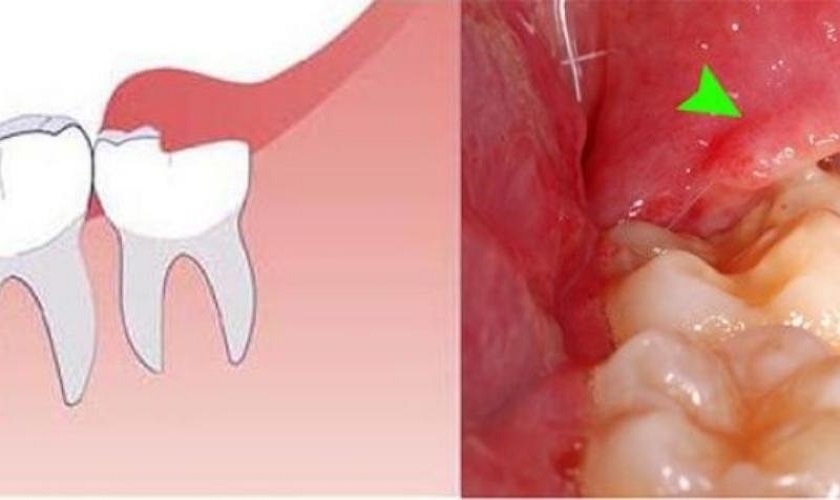

Lợi trùm là tên gọi phần lợi phủ phía trên răng và sẽ dần biến mất khi răng mọc lên. Chúng thường xuất hiện trong trường hợp mọc răng khôn – chiếc răng cuối cùng trên cung hàm. Mặc dù vậy, vẫn có trường hợp phần lợi này không biến mất và lẫn vào với răng hoặc phủ trên răng khiến răng không trồi ra ngoài được gây ra viêm lợi trùm và thậm chí là viêm có mủ. Các biện pháp điều trị viêm lợi trùm thường được áp dụng là nhổ răng khôn, dùng thuốc giảm đau hoặc cắt lợi trùm.

Cắt lợi trùm loại bỏ mô lợi phủ trên răng khôn

Viêm lợi trùm răng khôn có thể xảy ra nếu không được cắt bỏ kịp thời